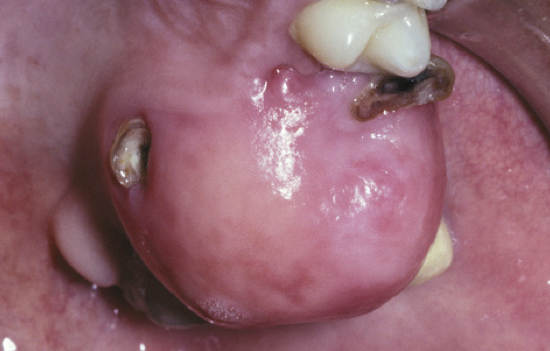

What is the likely Dx?

Peripheral ossifying fibroma.